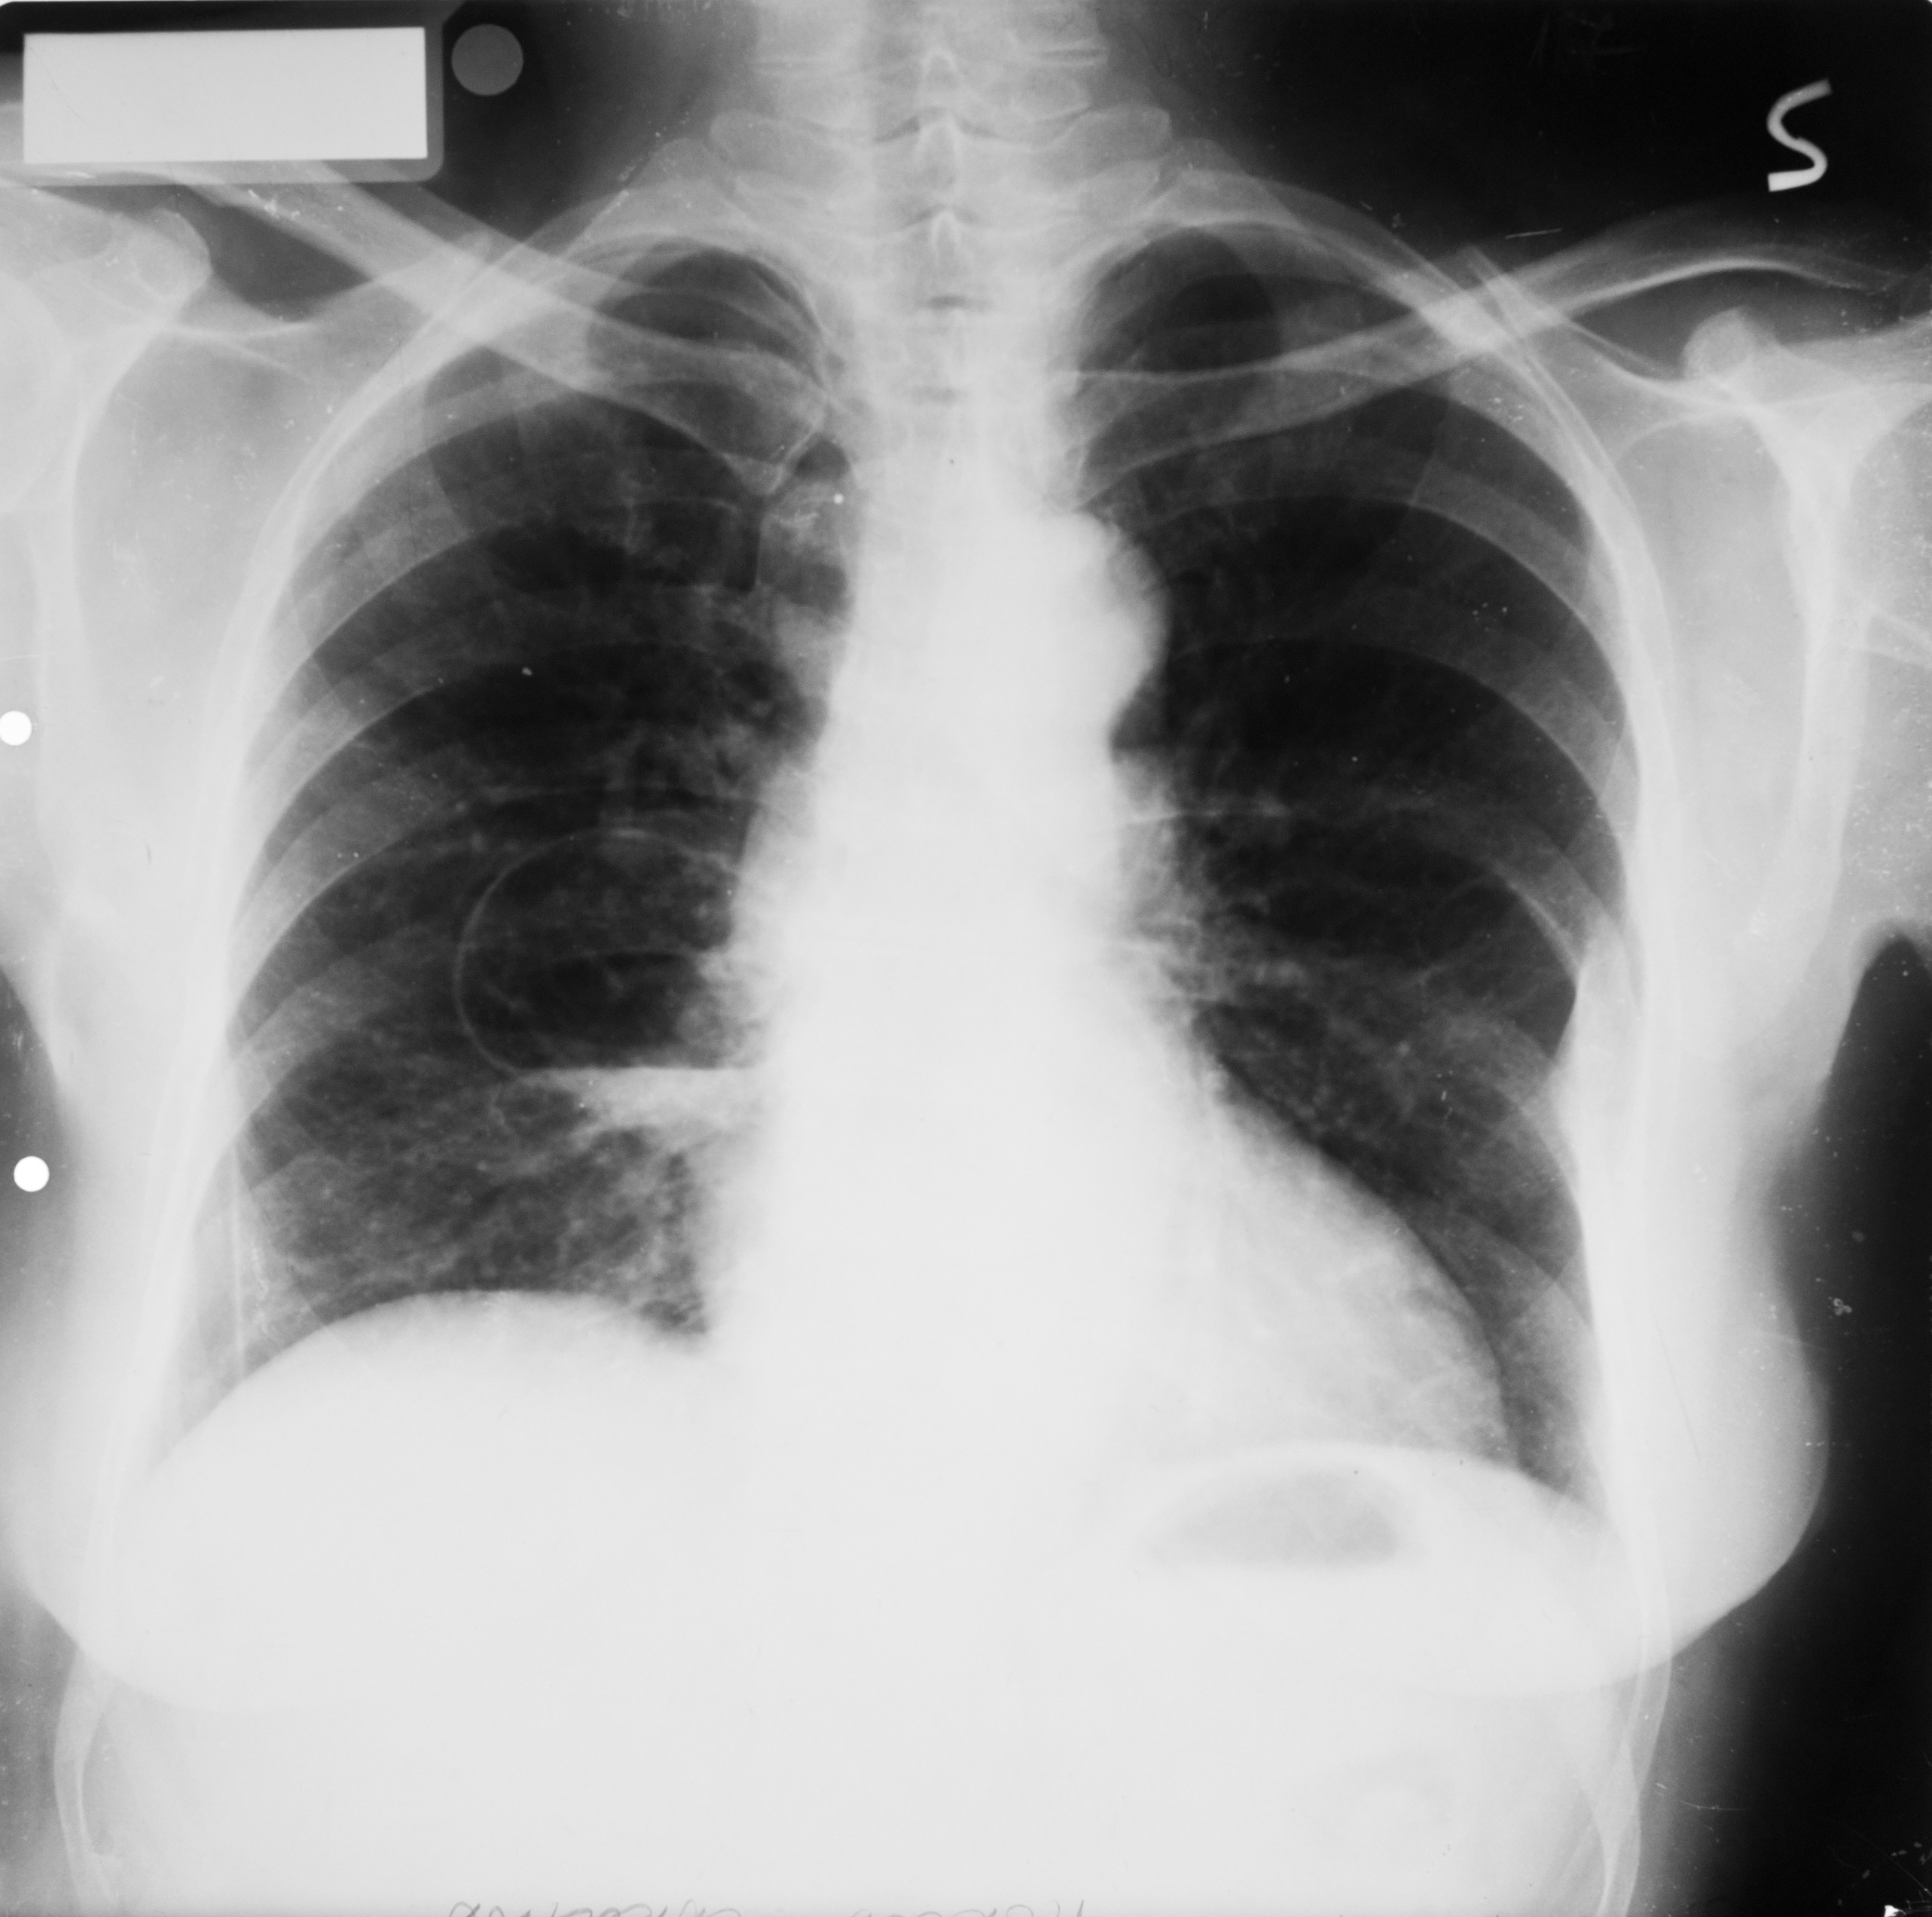

Rx toraco-mediastino-pleuro-pulmonară,incidența de față – vedem o imagine toracică normală (ITN) cu desen pulmonar,cu hil,fara nicio modificare patologică